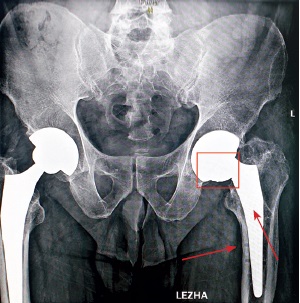

Sequential X-ray methods of research using plain pelvic radiography in the antero-posterior view revealed a satisfactory inclination of the acetabular component, a varus position of the femoral component of 10°, and a distortion of the endoprosthesis contours in the lower region of the acetabular component and the femoral neck component, which was regarded as a fracture of the ceramic liner or head that make up the bearings. Signs of a previously installed DHS surgical hardware, as well as channels from previously inserted cortical and dynamic screws, were visualized in the cortical area in the upper third of the diaphysis of the left femoral bone after removal in the diaphyseal and subtrochanteric regions (Fig. 1, 2).

Fig. 1. Overview X-ray of the hip joints: on the right — a total hip replacement with a cementless proximal fixation (2019); jn the left — a total hip replacement with a cementless proximal fixation. Dislocation of the elements of the bearing (highlighted in red). The arrows indicate the canals after removal of the screws

Multi-slice computed tomography (MSCT) revealed head decentration. Its correct shape was visualized, which only enabled us to assume its integrity; and a freely lying fragment of a ceramic liner in the neck area of the femoral component was noted. The retroversion was 23° with acetabular component malposition (Fig. 3).

Fig. 3. MSCT: a — frontal projection: decentration of the femoral component head, its correct shape and a fragment of the ceramic liner in the area of the femoral component neck (arrow) are visualized; b — axial projection: malposition of the acetabular component on the left — 23° retroversion

A fracture of the acetabular liner on the left was diagnosed (Fig. 4). A histological examination of the puncture sample was not performed since radiological diagnostic methods were sufficient.

Fig. 4. MSCT, sagittal projection: fracture of the ceramic liner